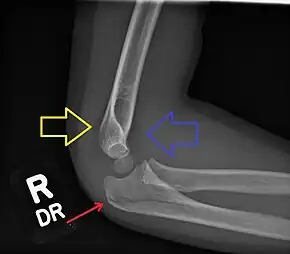

Fractured elbow in a child (ulnar shaft) with joint effusion of elbow

Normal elbow in same child, other side